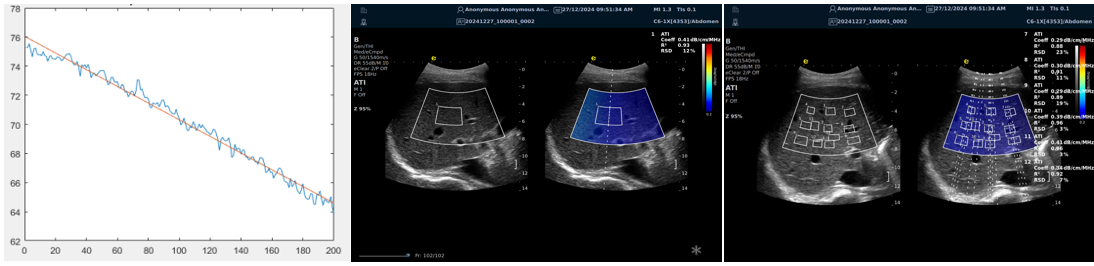

ATI高级声衰减成像

?独有的幅度损失的衰减方法ALA,准确性高,稳定性好,实时性好?业界唯一支持凸阵与线阵两种探头?支持多个取样框?提供两种显示单位

1b93bd09b343ed7a1e0b155407e34f4.png

肌骨领域的应用

?肌腱炎症或损伤的评估?肌肉拉伤的定位?关节磨损或炎症的诊断?骨质疏松的早期发现和监测

c8236a86e68d65834436e5fdd9b2629.png